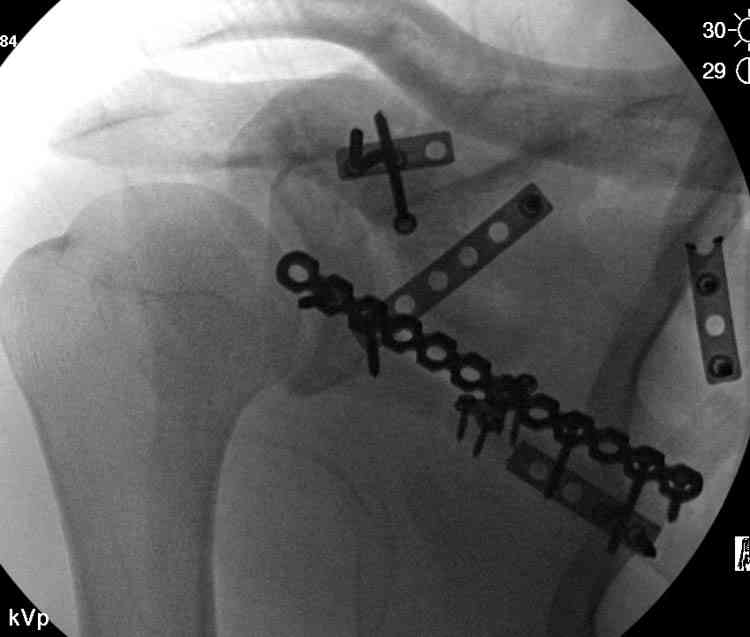

На снимке (№6 компьютерная томограмма и 3D №7) перелом клювовидного отростка.

Передним дельтопекторальным Bankart доступом намного легче провести фиксация отростка, но тогда репозиция и фиксация колонн затрудняется, поэтому был применен стандартный Judet задний доступ.

Репозицию смогли сделать пальцами через щель между

шейкой и телом лопатки (последний 3D снимок)

Двумя шурупами сзади на пластине (вместе шайбы)

провели удержание репозиции, а фиксацию провели

следующим косым шурупом.

Последующие этапы на снимках.